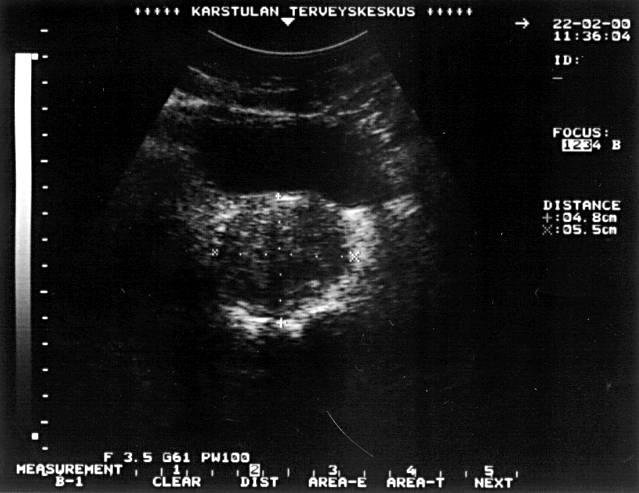

Prostatic Hyperplasia (Transverse Ultrasonographic Picture)

Prostatic hyperplasia (transverse ultrasonographic picture).Urinary retention in an elderly man was caused by a significantly enlarged prostate. The height of the prostate measures 4.8 cm and the width 5.5 cm. The length (in a longitudinal picture) measures 4.9 cm. The estimated prostatic size is 0.6 × 4.8 × 5.5 × 4.9 = 77 ml and the weight is about the same in grams.

Picture: Ilkka Kunnamo